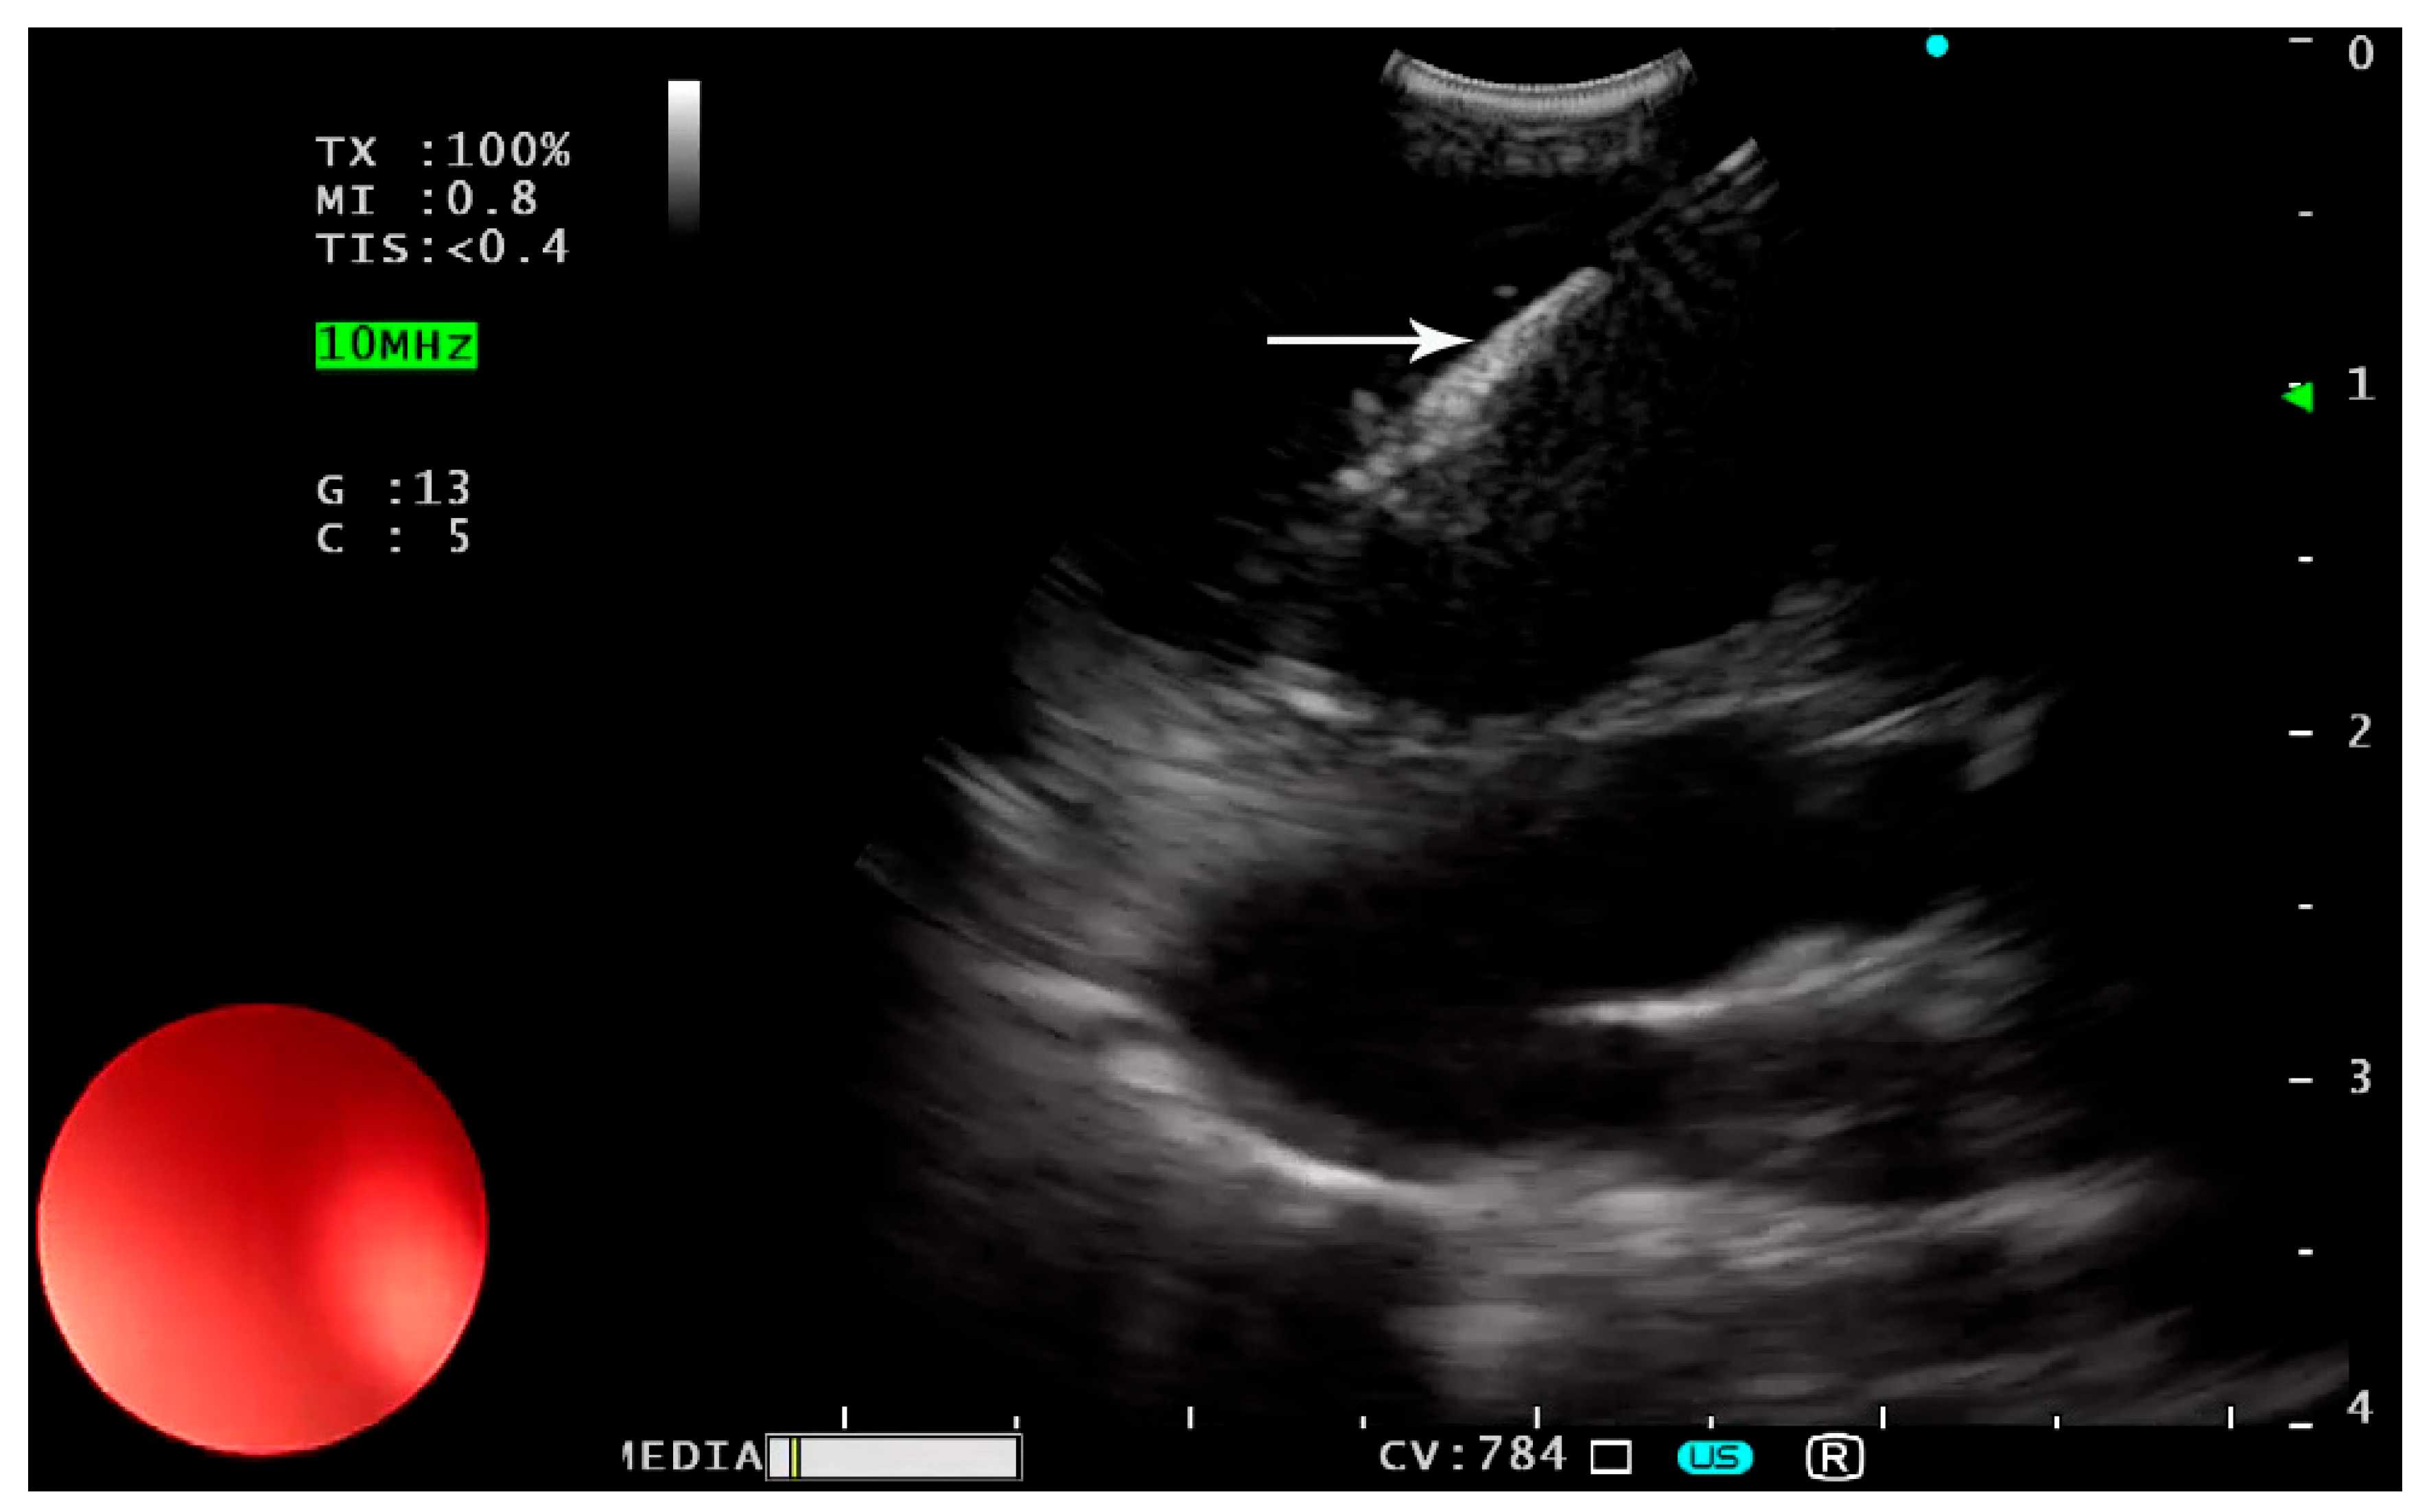

6.2. Inserting the Needle and Catheter Assembly

The sheath is advanced until it is visible on the screen. The puncture depth is adjusted and locked. Subsequently, the needle is precisely directed into the target under ultrasound visualization (Figure 2).

Figure 2. Insertion of the puncture needle (white arrow) into the target mass.